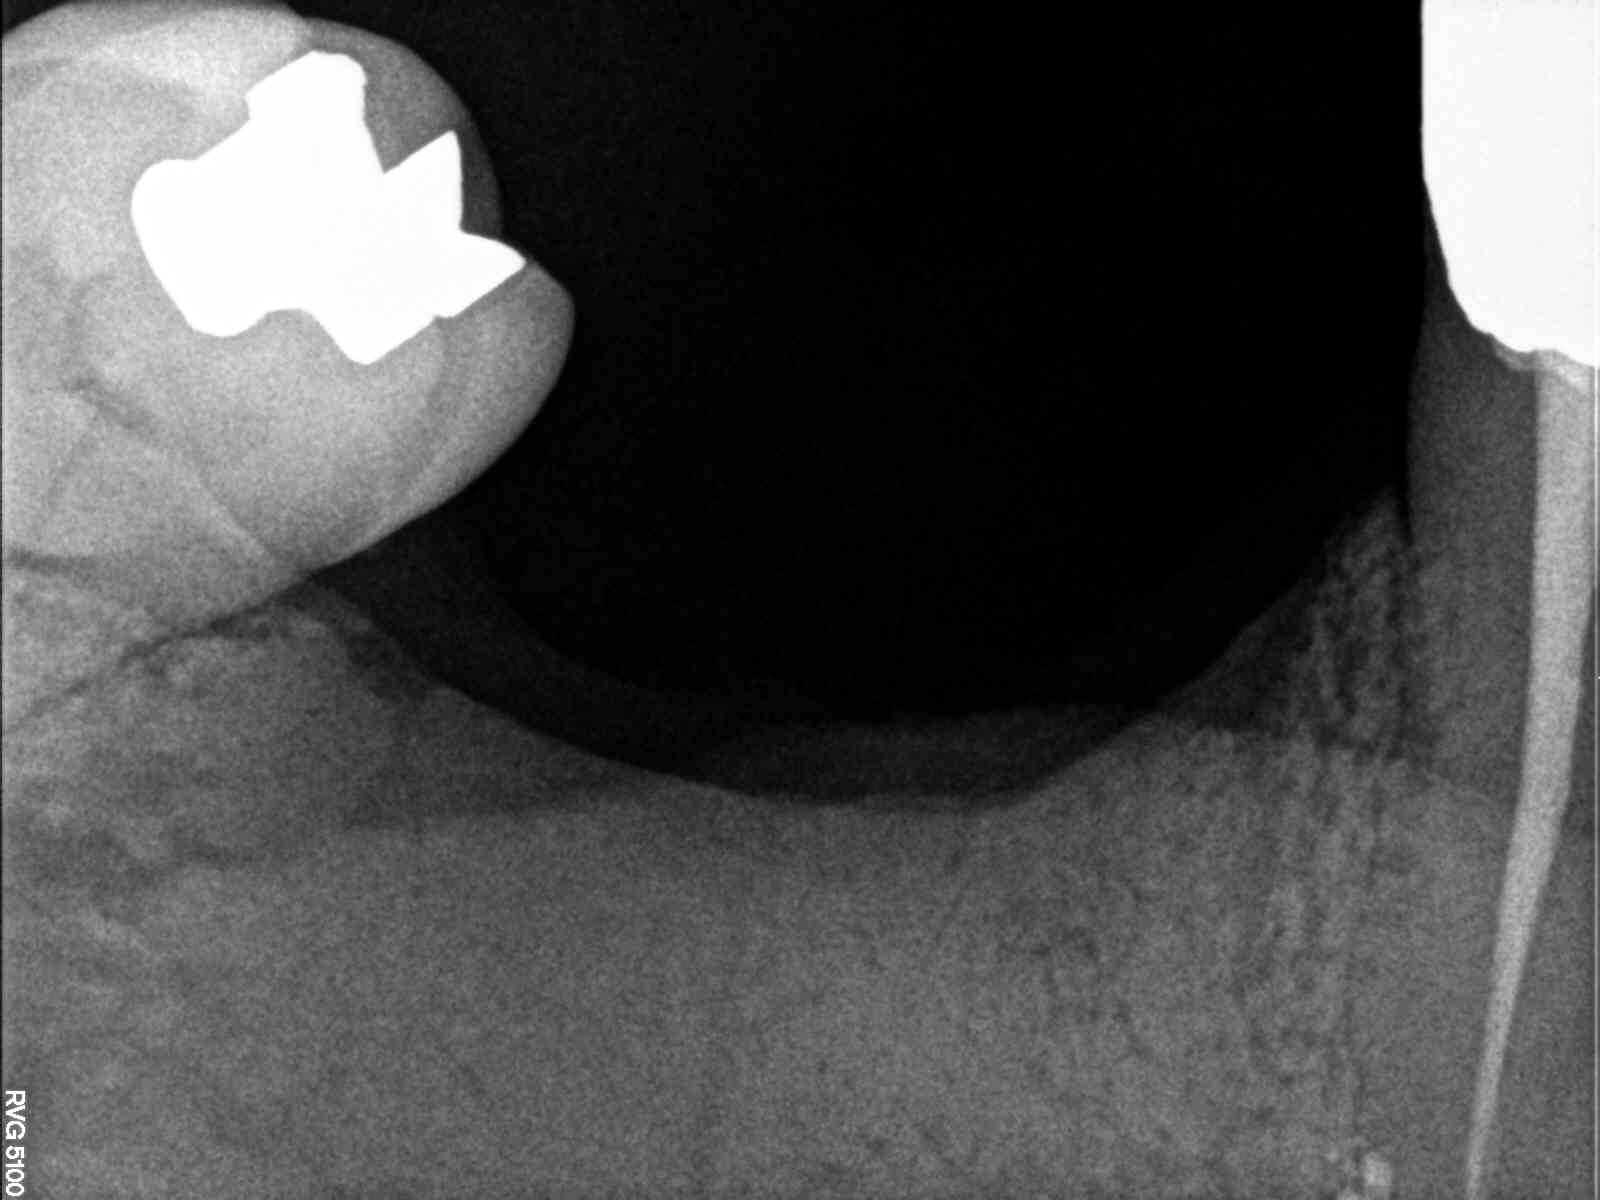

Découverte fortuite à la pano ... gamine de 17ans

Aucun signe clinique SAUF mobilité de 37 qui m'a inquiété .

c est l ameloblastome ???

La maxillo m'a fait un retour en précisant suspicion d'améloblastome.

Update : C'est bien un améloblastome.

Mandibulectomie sectorielle prévue avec reconstitution fibulaire ..

C’est effrayant la vitesse à laquelle ça a progressé 😔